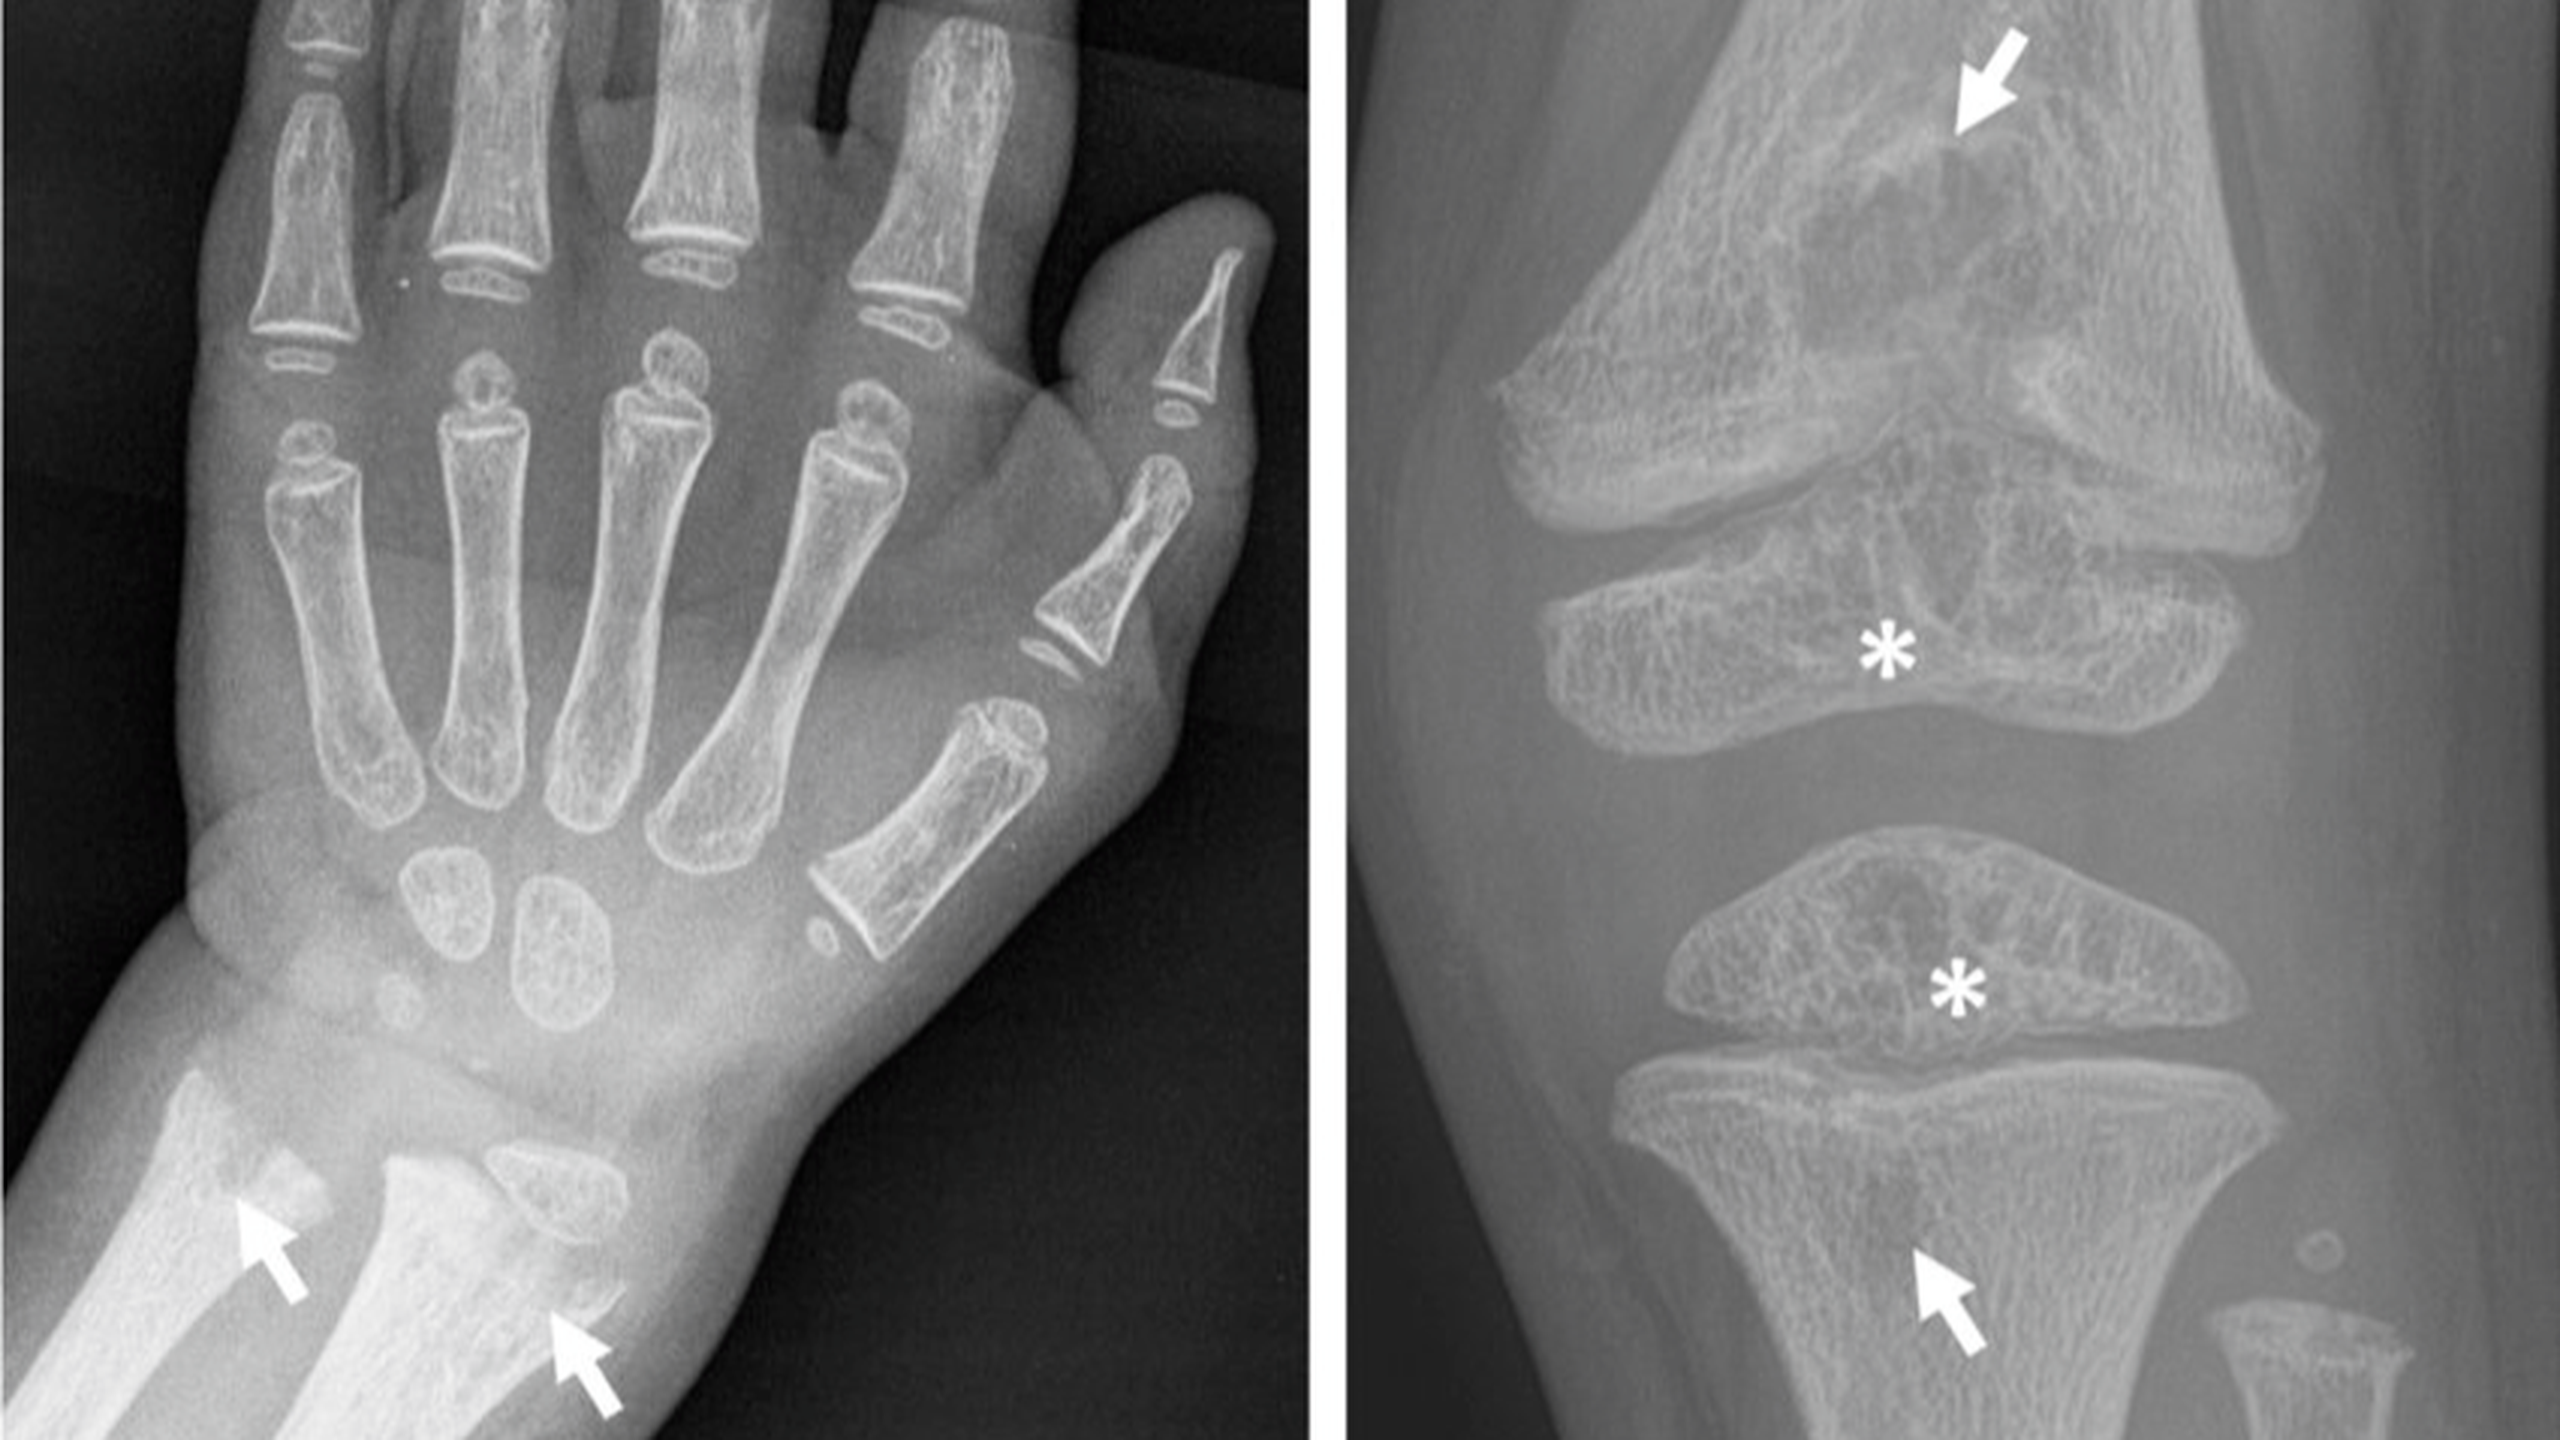

Bệnh nhân ở dạng trẻ sơ sinh có thể trông bình thường khi mới sinh. Tuy nhiên, các dấu hiệu lâm sàng của chứng giảm phosphat sẽ xuất hiện trong sáu tháng đầu. Dạng này cũng có các biến chứng về hô hấp do biến dạng xương ở ngực. Chụp X quang cho thấy sự khử khoáng lan rộng. Tăng canxi máu cũng xuất hiện kèm bú kém, chán ăn, nôn mửa, hạ huyết áp, khát nước, đa niệu, mất nước và táo bón. Tăng bài tiết canxi có thể dẫn đến tổn thương thận.

Sự di truyền của bệnh này rất phức tạp do kiểu di truyền khác nhau (di truyền trội trên nhiễm sắc thể thường hoặc di truyền lặn trên nhiễm sắc thể thường). Bệnh này là do đột biến gen phosphatase kiềm ở gan/xương/thận (ALPL) mã hóa phosphatase kiềm không đặc hiệu cho mô (TNAP). Chẩn đoán bệnh dựa trên các xét nghiệm sinh hóa máu và giải trình tự DNA của gen ALPL.

Hoạt tính phosphatase kiềm (AP) trong huyết thanh giảm rõ rệt ở tình trạng giảm phosphatase, trong khi phosphoetanolamine (PEA) trong nước tiểu tăng lên. Bằng cách sử dụng phương pháp giải trình tự DNA có khoảng 95% đột biến được phát hiện ở tình trạng giảm phosphat nặng (chu sinh và trẻ sơ sinh).